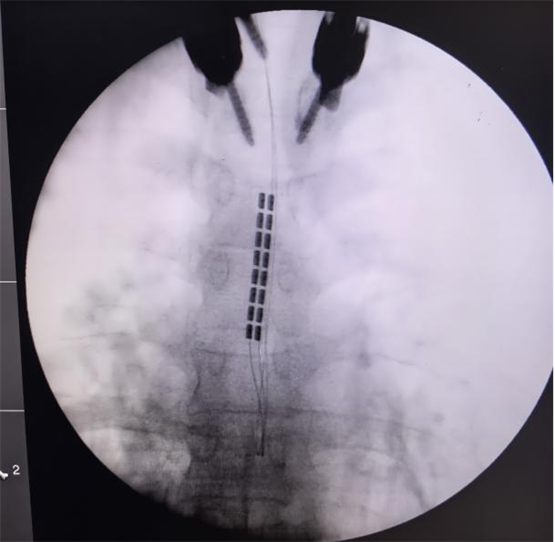

經(jīng)過(guò)嚴(yán)格的術(shù)前討論,團(tuán)隊(duì)決定為孫女士施行頸段脊髓電刺激(SCS)植入術(shù)。手術(shù)由陳菊祥教授主刀,在C臂X光機(jī)精準(zhǔn)引導(dǎo)下,將刺激電極植入頸髓(C2-C4水平)硬膜外腔的中線位置。

為避免對(duì)患者脊髓功能造成任何醫(yī)源性損傷,團(tuán)隊(duì)在術(shù)中全程采用了影像導(dǎo)航系統(tǒng),以及多模式神經(jīng)電生理監(jiān)測(cè),包括連續(xù)腦電圖(EEG)、體感誘發(fā)電位(SSEP)等,實(shí)時(shí)監(jiān)控神經(jīng)系統(tǒng)功能狀態(tài),為手術(shù)安全上了“雙保險(xiǎn)”。“手術(shù)精度要求達(dá)到毫米級(jí),確實(shí)是刀尖上起舞,“陳菊祥教授如此形容,”術(shù)后我立刻查看了影像,確認(rèn)電極位置精準(zhǔn)?!?/p>